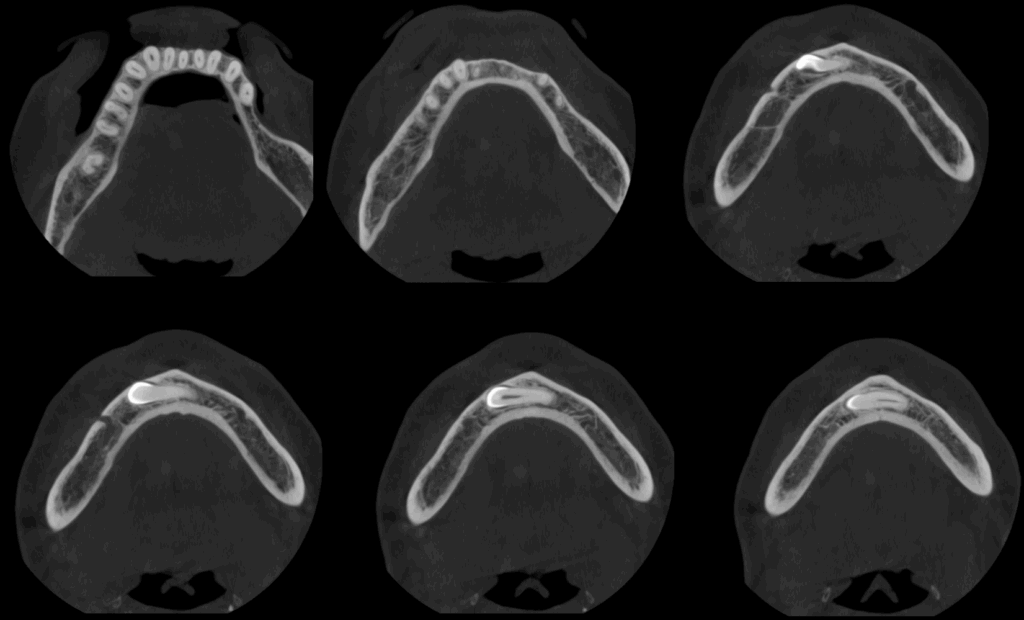

A la evaluación de la tomografía cone beam de campo mediano se puede observar que dicha pieza se encuentra caudal al ápice de las piezas 32, 31, 41, 42 y 43 con la porción coronaria en contacto y adelgazando la tabla ósea vestibular y la porción radicular se encuentra equidistante a ambas tablas óseas y la presencia de un foramen lingual. Se descartar cualquier relación con piezas dentarias vecinas

CORTES AXIALES